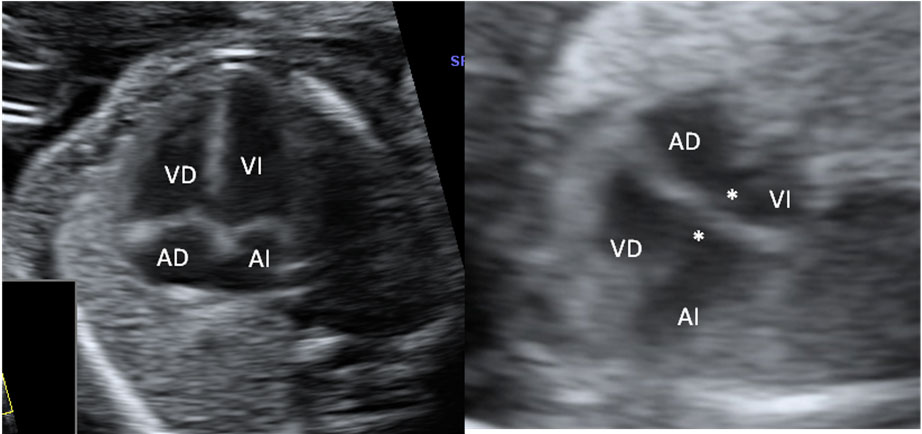

En la imagen ecográfica podemos ver el corte de la cabeza fetal donde se muestra la medición de un ventrículo cerebral aumentado de tamaño (o ventriculomegalia).